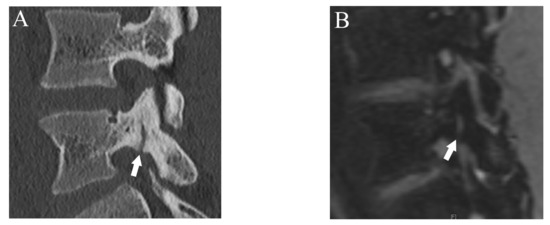

Figure 7.

The case that lower fracture grade was assigned by DESS than CT. (A) CT suggests an incomplete fracture which was consistent with grade 2 (arrow). (B) DESS shows a subtle high signal in the cortex of the pars interarticularis and evaluated as grade 1 (arrow). BME is also detected (arrowhead).

Agreement of fracture grading with CT showed excellent (Kappa = 0.90 (95% confidence interval (CI): 0.84, 0.96)) on DESS but T1WI showed substantial (Kappa = 0.67 (95% CI: 0.61, 0.73)) agreement. Compared to reference fracture grade created by CT, nine cases were assigned a lower grade by DESS, whereas three were assigned a higher grade (Figure 7).